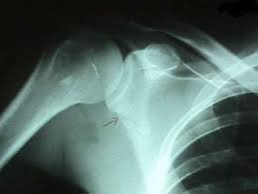

어깨뼈 골절은 어깨 주변을 구성하는 여러 뼈 중 하나가 부러지는 상태를 의미합니다. 어깨는 단순한 관절이 아니라 여러 뼈와 인대, 근육이 복합적으로 연결된 구조이기 때문에 골절의 종류도 다양하게 나타납니다. 흔히 발생하는 골절 위치는 견갑골, 쇄골, 상완골 근위부입니다. 특히 낙상 사고나 교통사고에서는 상완골 근위부 골절이 자주 발생합니다.

이 중에서도 상완골 근위부 골절은 고령자 낙상 사고에서 매우 흔하게 나타나는 골절이며, 경우에 따라 금속 핀이나 금속 플레이트를 이용한 고정 수술이 필요할 수 있습니다.

- 초기 진단

- X-ray 촬영

- CT 검사

- 골절 위치 확인